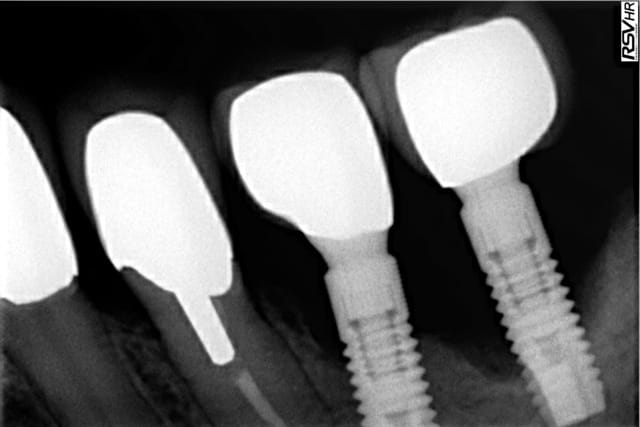

Il semblerait que ce soient des implants Astra OsseoSpeed TX.

les deux tiers de l'implant distal ne sont plus intégrés ( au moins 5mm de macro spires plus les micro spires du col implantaires).

Les cols implantaires ne sont pas au même niveau, le recouvrement de la greffe sera difficile à obtenir.

espérer une décontamination de la surface implantaire,un comblement, une bonne couverture du site greffé avec une bonne cicatrisation semble assez aléatoire chez un patient fumeur compte tenu de la perte osseuse importante.

Ce n'est pas une perte cratérisé avec parois résiduelles mais une perte horizontale.

Si l'intervention échoue, la perte osseuse finale sera plus importante.

dans le cas présent: implant astra connectivité éprouvé, switch platform je pense que la cause serait le stress...

Occlusion porcelaine sur porcelaine...et implants non jumelés